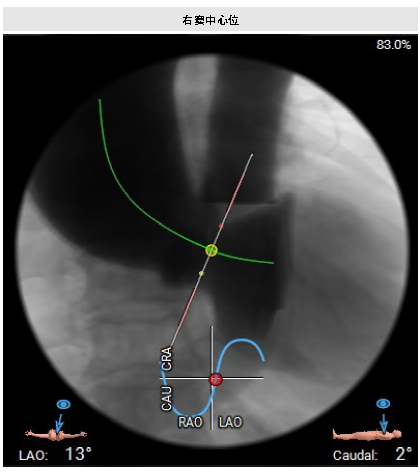

左心评估:左室扩张,室间隔增厚,心尖变薄。瓣环水平夹角68°,提示横位心。

选型:BAV 18球囊预扩,Prizvalve®球扩瓣THV23,右侧股主入路22F大鞘。

策略:减容、2-8定位释放。